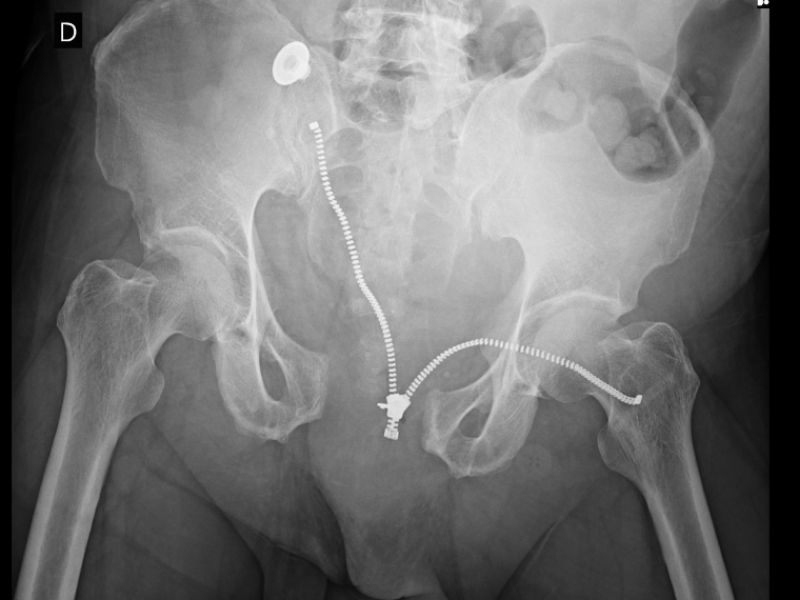

As fraturas open book são fraturas na qual ocorre abertura de sínfise púbica acima de 2,5cm e estão relacionadas a mecanismo de compressão antero-posterior como um atropelamento frontal, por carro, ônibus, etc.

Essas fraturas são as mais temidas da Ortopedia como um todo, pois essa abertura da sínfise púbica indica indiretamente que houve lesão de vasos intrapélvicos e a cavidade pélvica não possui mais a capacidade de tamponamento sanguíneo de forma que o paciente, se não for tratado de imediato por um ortopedista, corre o risco de hemorragia e até óbito. Essas fraturas possuem cerca de 50% de mortalidade.